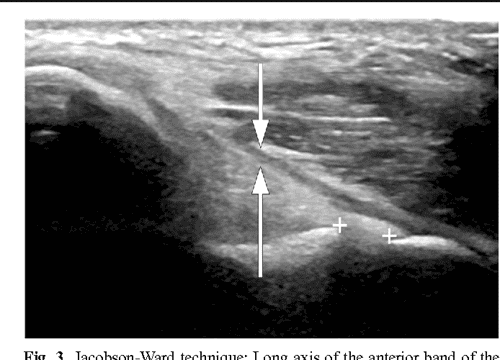

Ultrasound evaluation of the ulnar collateral ligament of Source: semanticscholar.org